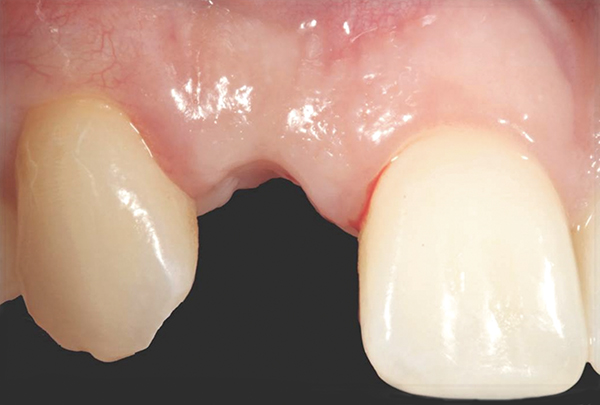

Fig 18. The final restoration after 4 months.

Figure 18